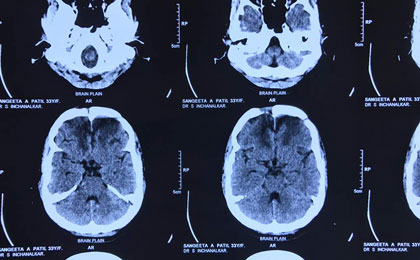

Brain Tumor Surgery  14/02/2019

frontal epidermoid pre t2w

• frontal epidermoid pre t2w

frontal epidermoid pre diffusion

• frontal epidermoid pre diffusion